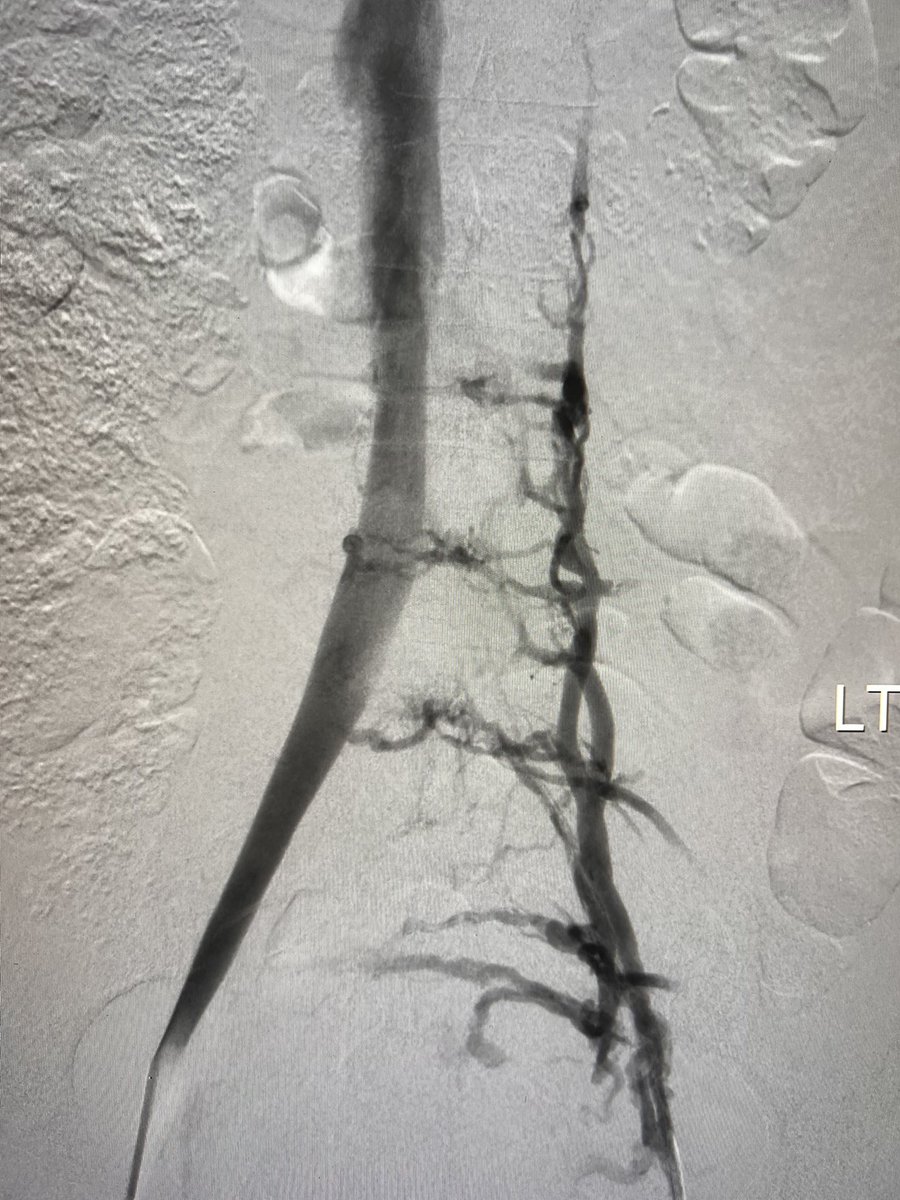

@ChengaziMD Thanks man! This is definitely something you can learn and apply. Did this w/ SI-Bone iFuse Torq screws, take a look at their stuff. They have great clinical support and easy to see how to translate their system for fracture stabilization